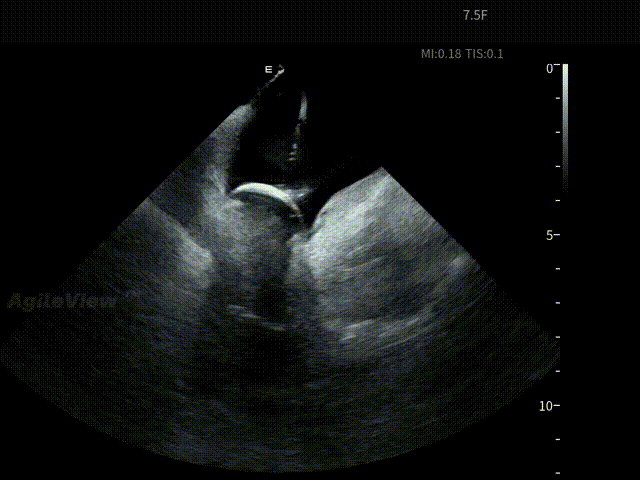

顶部线第一次消融

第二次顶部线消融